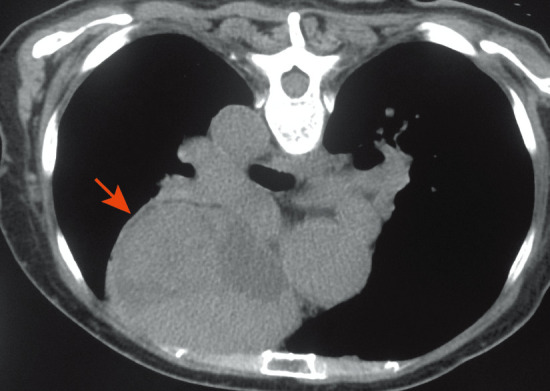

患者,女,77岁。主因“发热、咳嗽、咳痰20 d”于2014年12月30日入院。患者2年前因“头晕、四肢麻木”而就诊,血常规示WBC 5.2×109/L,中性粒细胞(N)2.3×109/L,HGB 220 g/L,PLT 270×109/L,骨髓象:增生活跃,红系占0.380,粒系占0.320,成熟受阻。骨髓活检:增生大致正常,粒系各阶段细胞均可见(散在或小簇分布),红系增生(以中晚红为主),巨核细胞计数正常范围,可见胞体大、多分叶巨核细胞。JAK2V617F阳性,BCR-ABL阴性。胸部CT:前上纵隔囊实性占位病灶。诊断:PV,胸腺瘤?先后给予羟基脲(0.5 g,每日3次,共1周)、重组人干扰素α-1b(300万U,每周3次,共2周)治疗,均出现粒细胞缺乏。后间断给予放血治疗。考虑手术风险(胸腺瘤侵犯主动脉壁),未行手术治疗。既往史:高血压病3级(极高危)8年,长期服用硝苯地平缓释片治疗,血压控制可。入院时查体:体温38.1 °C,血压120/74 mmHg(1 mmHg=0.133 kPa),颜面潮红,球结膜充血,口腔黏膜见多发溃疡(无白膜覆盖),浅表淋巴结未触及肿大,胸骨无压痛,双肺呼吸音清晰,未闻及干湿性啰音,心脏听诊正常,肝、脾肋缘下未及,双下肢无水肿。实验室检查:血常规:WBC 2.2×109/L,N 0.40×109/L,RBC 7.22×1012/L,HGB 178 g/L,红细胞比容(HCT) 0.548, PLT 281.8×109/L;尿常规、肝肾功、电解质、红细胞沉降率正常;腺病毒、呼吸道合胞病毒、甲型流感病毒、乙型流感病毒、副流感病毒、EB病毒、巨细胞病毒检测均阴性;降钙素原<0.05 µg/L;血培养、尿培养均阴性;抗中性粒细胞胞质抗体谱阴性;淋巴细胞亚群:CD3+细胞96.7%(正常参考值65.0%~79.0%),CD4+细胞18.3%(正常参考值34.0%~52.0%),CD8+细胞72.3%(正常参考值21.0%~39.0%),CD4+/CD8+细胞比值为0.25(正常参考值1.00~2.00),NK细胞2.6%(正常参考值10.0%~19.8%),B细胞0.1%(正常参考值9.0%~14.1%)。骨髄象:增生减低,粒系占0.110,红系占0.560(以中、晚幼红为主,成熟红细胞大小不等,可见嗜多染),淋巴细胞占0.265,全片见10个巨核细胞,血小板成堆(图1)。骨髄活检:增生较活跃,脂肪细胞略少,粒系各阶段均可见,散在或小簇分布,易见嗜酸粒细胞;红系比例增高,以中晚红为主,散在或成簇分布,可见双核、分裂相、类巨变表现;巨核细胞计数正常范围,以分叶核为主;铁染色(−),银染色(+);融合基因:JAK2 V617F阳性,BCR-ABL阴性。染色体核型正常。胸部CT(图2):两肺慢性炎症改变,左肺下叶胸膜下多发小结节影,考虑炎性结节;两肺多发微小结节影,两肺下叶充气不均,考虑小气道病变;前上纵隔占位(胸腺瘤?)。心电图未见异常。腹部B超声示:脾大,肋间厚14 cm,长径13 cm,回声均匀。临床诊断:PV,肺炎,粒细胞缺乏症,胸腺瘤,高血压病3级。

图2. 胸部CT示前上纵隔占位病变(箭头所示).